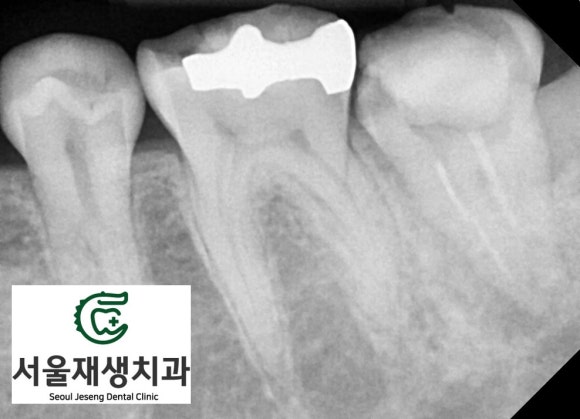

치아 안에는 예전에 신경치료 재료 (하얀 줄기)가 남아있고,

치아 내부에서 시작된 염증 때문에

뿌리를 감싸는 뼈가 모두 녹았습니다.

실제로도 치아는 많이 흔들리는 상태였습니다.